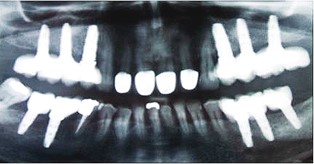

Implantes dentales

Los implantes dentales son estructuras metálicas que se anclan al hueso maxilar o mandibular, y sobre las que se fijan prótesis dentales. El implante dental es por tanto la raíz del nuevo diente, y la prótesis dental que se pone encima es la nueva corona del diente.

Los implantes dentales se utilizan desde hace más de 40 años para restaurar los dientes perdidos.